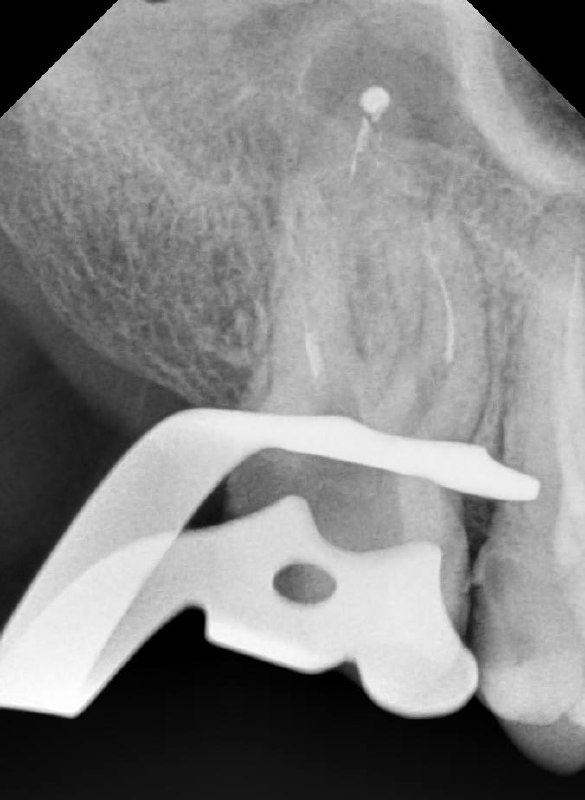

📸 На фото представлен клинический случай. Пациент обратился в нашу клинику с жалобой на боль при надкусывании 😬. При первичной диагностике был выявлен сломанный инструмент в корневом канале, который привёл к воспалению 🦠.

На следующих снимках видно, что отломок инструмента был успешно извлечён. Все каналы были пройдены, механически обработаны под микроскопом 🔬 и запломбированы.

Работа врача -стоматолога -микроскописта Овчинниковой М.И